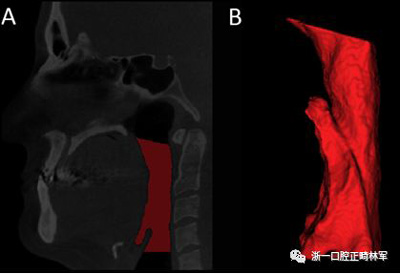

咽腔體積(PS體積)的分析是從三維模型進(jìn)行的。三維模型的重建采用軟件Insight ITK-SNAP(版本2.4.0; Cognitica,Philadelphia,Pa)的半自動(dòng)分割模式建立,該模型以立方毫米測(cè)量結(jié)構(gòu)的體積。本研究中測(cè)量的體積對(duì)應(yīng)于口咽和下咽部之間的聯(lián)合。為此,我們按照Park等描述的解剖學(xué)定義確定了從后鼻棘到第一頸椎的最低點(diǎn)的上部參考線,以及在垂直于內(nèi)側(cè)矢狀面的第四頸椎最低點(diǎn)上描繪的下部參考線(圖5)。

圖5.A,使用文本中描述的參考點(diǎn)對(duì)咽腔進(jìn)行分割(紅色); B,口咽和下咽部之間的聯(lián)合體積。